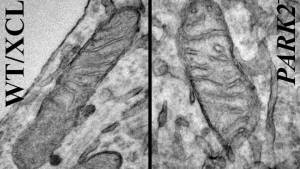

Mitochondria from iPSC-derived neurons. On the left is a neuron derived from a healthy individual, while the image on the right shows a neuron derived from someone with the Park2 mutation, the most common mutation in Parkinson’s disease (Credit: Akos Gerencser)

And by using this technology, the Buck Institute team confirmed that the same process that occurred in fruit fly cells also occurred in human cells. Specifically, the team found that a particular mutation in these cells, called Park2, altered both the structure and function of mitochondria inside each cell, setting off a chain reaction that leads to the neurons’ inability to produce dopamine and, ultimately, the death of the neuron itself.